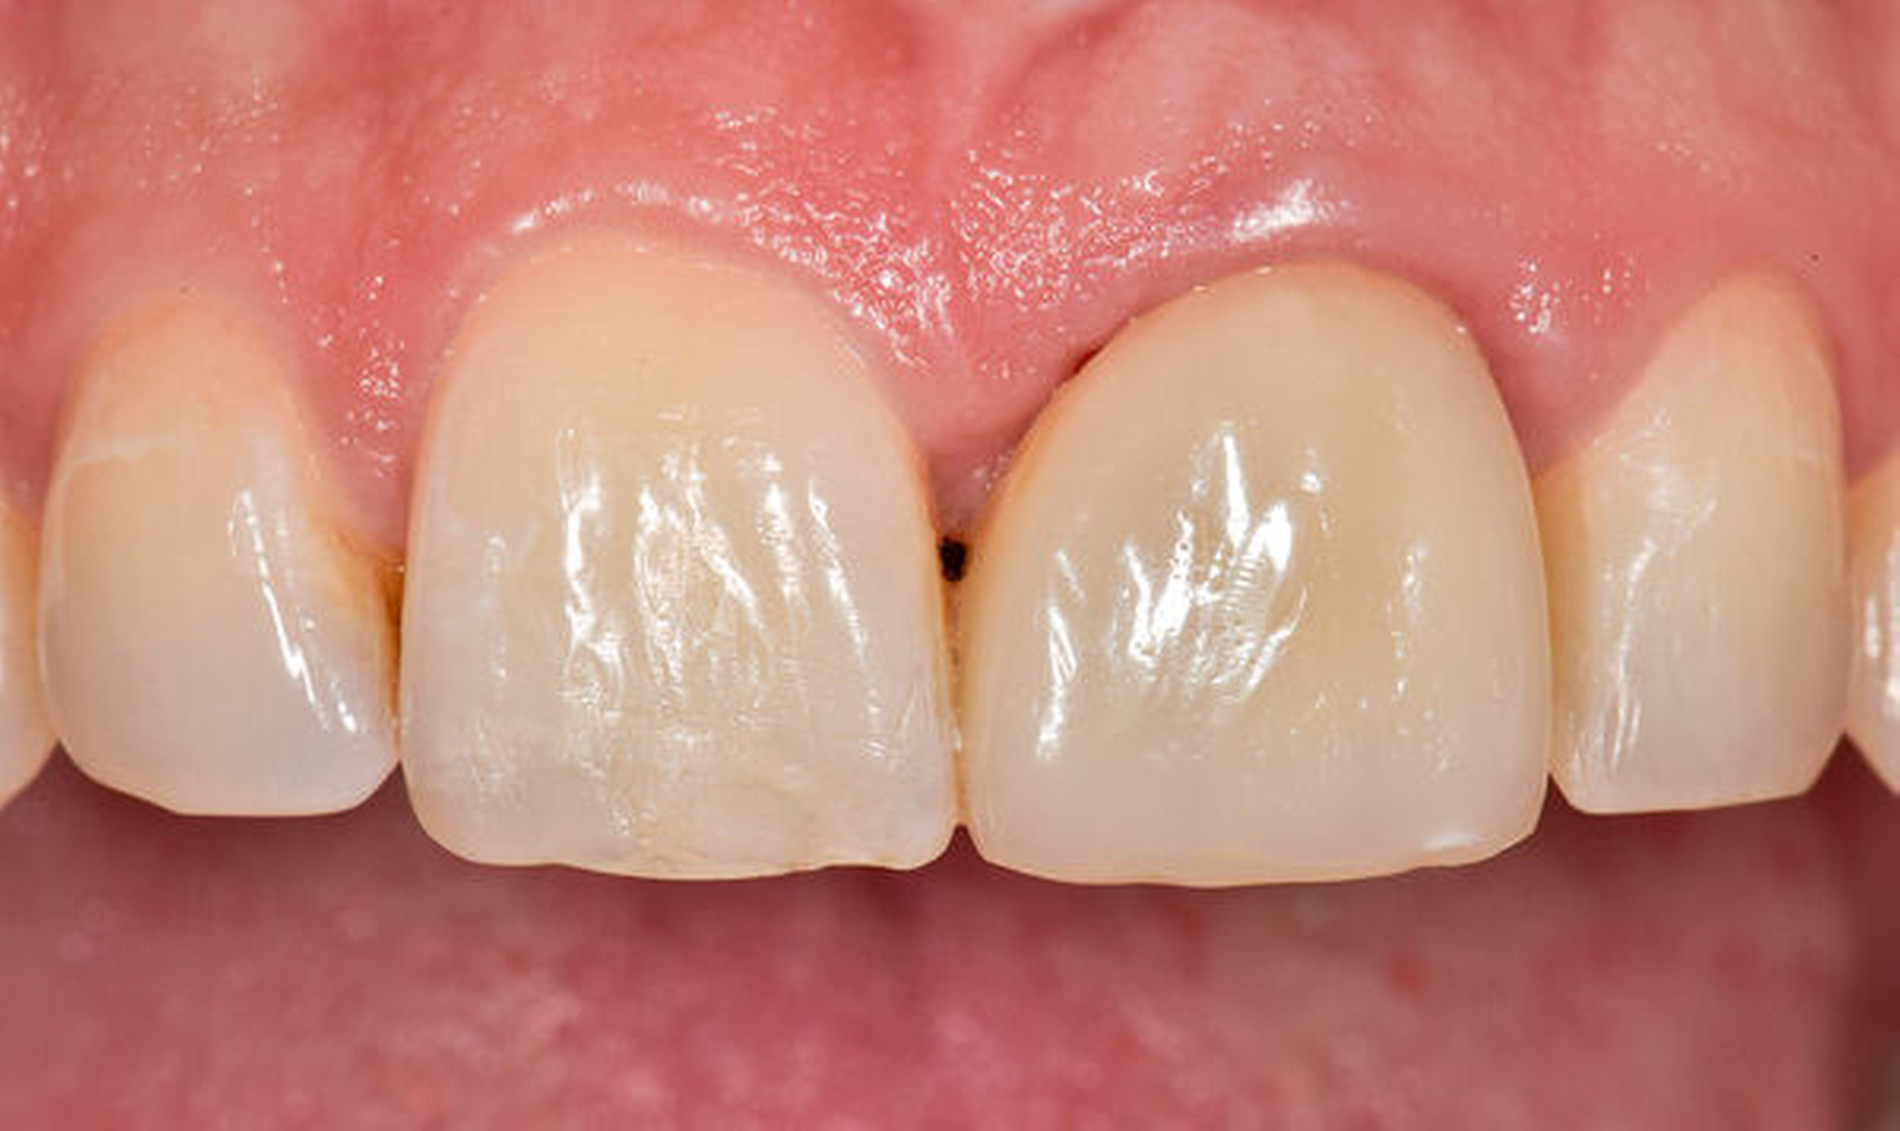

Als Vorteil der chirurgischen Extrusion im Vergleich zur chirurgischen Kronenverlängerung wird das deutlich vorteilhaftere ästhetische Resultat mit Erhalt von Weichgewebe und Papille angegeben [Llaquet et al., 2021]. Diese Gewebe werden geschont und erfahren keine Traumata, wie dies bei einer chirurgischen Kronenverlängerung unvermeidbar geschieht [Behring et al., 2017; Lanning et al., 2003]. Indiziert ist die Extrusion vor allem bei einwurzeligen Zähnen in ästhetisch relevanten Bereichen. Biologisch betrachtet liegen solide und langzeitstabile Resultate zu dieser Technik vor. Einer aktuellen Übersichtsarbeit zufolge, basierend auf elf klinischen Studien, kann ein Behandlungserfolg mit parodontaler Heilung der Wurzel in 95 bis 100 Prozent der Fälle nach chirurgischer Extrusion erwartet werden [Plotino et al., 2020]. Eine weitere Übersichtsarbeit fokussiert auf die Häufigkeit von Komplikationen nach chirurgischer Extrusion. Den verfügbaren Daten zufolge liegt das Risiko für Zahnverlust bei fünf Prozent, das für progressive Wurzelresorptionen bei drei Prozent. Ein marginaler Knochenabbau ist ebenfalls eine seltene Komplikation (weniger als vier Prozent der Fälle). Nicht progressive Wurzelresorptionen werden mit circa 30 Prozent zwar recht häufig beobachtet, diese sind allerdings selbstlimitierend und gefährden nicht den Zahnerhalt [Elkhadem et al., 2014].

Eine sehr gewebeschonende, jedoch zeitlich aufwendigere Technik zur Generierung eines Ferrule-Effekts bei tief zerstörten Zähnen ist die kieferorthopädische Extrusion [Bondemark et al., 1997; Brandt, 2016; Krastl, 2004; Carvalho et al., 2006; Hergt und Christofzik, 2017; Mehl et al., 2017; Wirsching, 2011]. Diese Technik ist prädestiniert für die ästhetische Zone, da hier im Gegensatz zu anderen invasiveren Techniken kein Gewebeverlust auftritt. Vielmehr kann durch den langsamen Extrusionszug vermittelt über den parodontalen Faserapparat eine Migration des Hart- und Weichgewebes (falls gewünscht) induziert werden. Wird während der Extrusionsphase das parodontale Ligament regelmäßig durchtrennt, findet folglich keine Gewebsmigration statt [Carvalho et al., 2006].